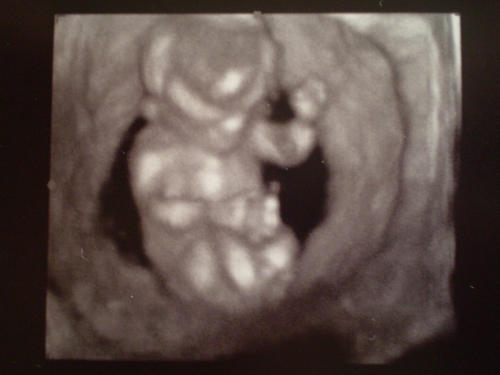

Pandababa oldalról a buksija( itt nézték a tarkóredő méretét):

Kép

És ez volt a 4D csak nem kaptunk színes képet:

Ez csodálatos, milyen szépen látszik a kezecskéje, lábikója, feje, minden, nem gondoltam volna, hogy ilyen szép képet tudnak készíteni 12 hetesen?!